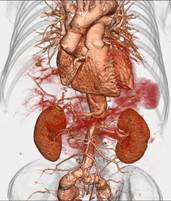

心血管疾病筛查

心脏及冠状动脉:

高分辨冠状动脉软斑块和支架

320排螺旋CT具备16cm宽覆盖探测器,实现动态容积扫描,360度的各向同性采集能力及[email protected]%密度分辨率的量子探测器,一次心跳全心脏采集,一圈扫描器官成像,一次检查完成多重任务,实现真正的动态容积体灌注及心脏、神经一站式检查;西门子Flash炫速CT扫描系统,具备两套同时旋转的X射线球管及探测器,实现了43cm/s的极快CT扫描速度和75 ms的时间分辨率,完成全胸扫描仅需0.6秒,使得患者做心脏扫描时无须食用β-受体阻滞药,亦无须屏气,并可实现低于1mSv的超低辐射剂量,配置第二代双能量、宽151级纯化能谱,组织鉴别能力进一步提高,可开展多达10余种双能量成像应用。